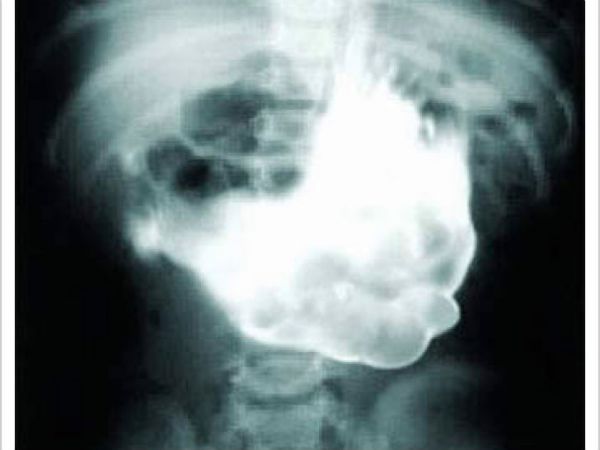

В одну из китайских больниц пришел мужчина с жалобами на боли в животе. Врачи сделали рентгеновский снимок и обнаружили стеклянную бутылку в желудке.